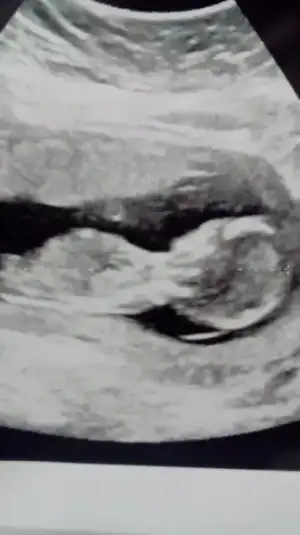

Kız sanki. 14. Hafta göstermedi mi?Hadi bende paylaşıyım ultrasonumu :) cinsiyet tahminlerinizi bekliyorum hatunlar

Kız sanki. 14. Hafta göstermedi mi?

aynen sağlıklı ve hayırlı bir evlat olsunda inşallah hiç farketmez:)hadi insaallh cnmm saglikli olsunda hic onmli degill ama biz merakli anneleriz yaa